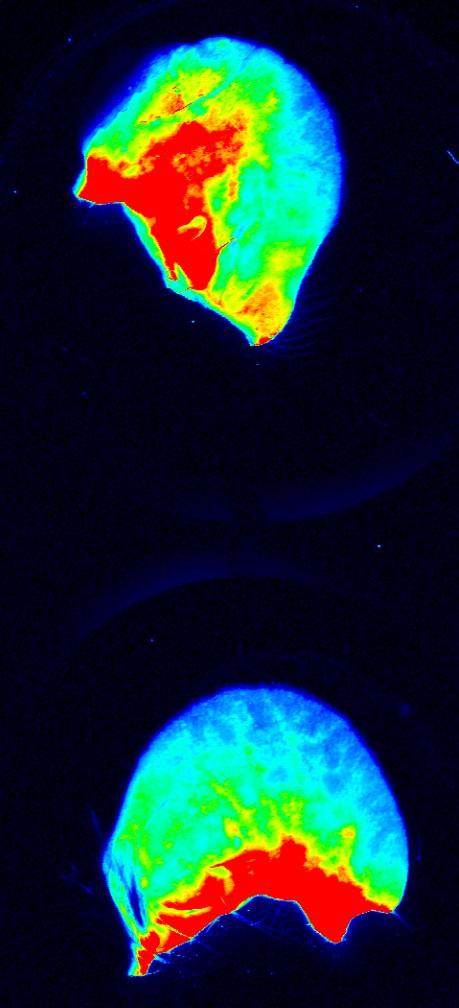

They further observed that mosquito saliva increases the permeability (i.e., the leakiness) of endothelial cells that line blood vessels. They designed an experiment to examine permeability, and found that the presence of saliva allowed markers to leak out of the blood vessels at the injection site and into the surrounding tissue in the ear. The same is presumably true for DENV infection in the presence of mosquito saliva.